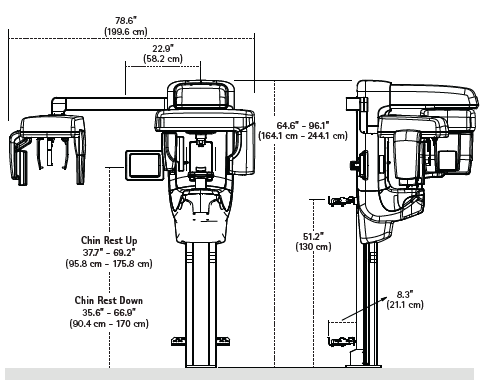

X-Ray System Incudes: